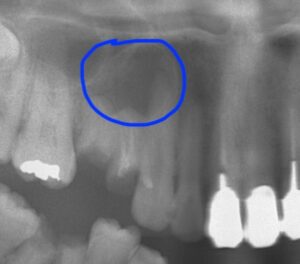

レントゲンでは青○の部分に嚢胞があります。